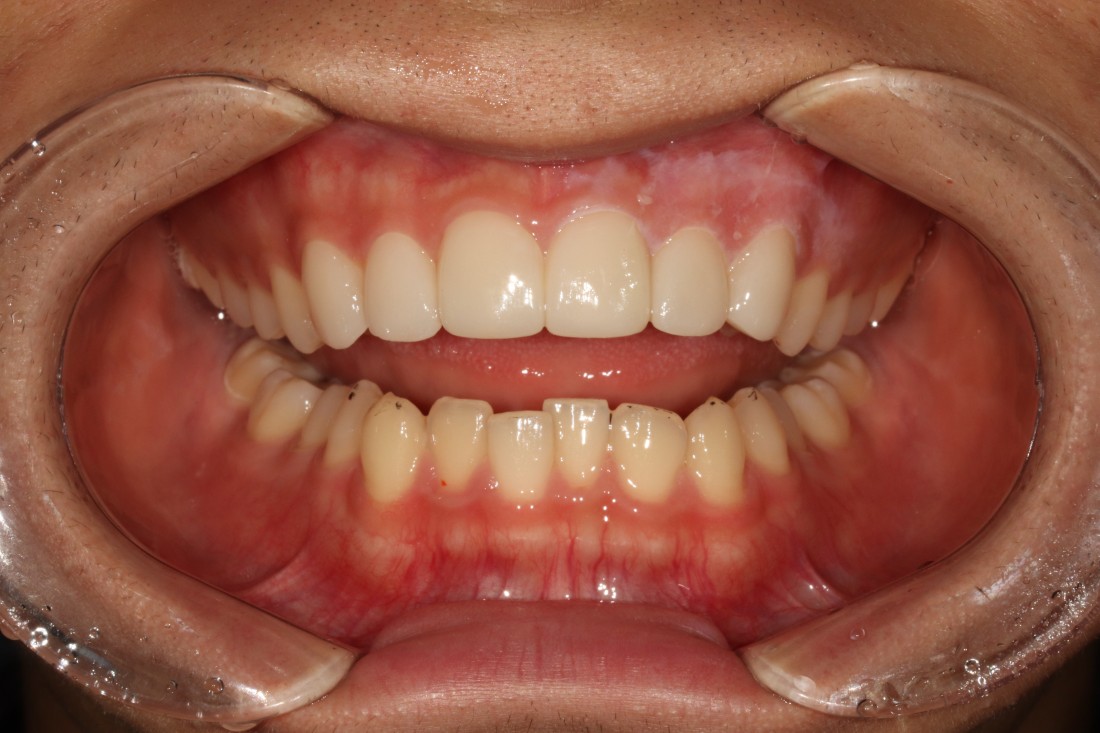

광주 라미네이트 치과에 방문해주신

40대 여성 고객님의 케이스입니다.

앞니 사이에 충치 치료로

검게 변색된 부분이

오랜시간 컴플렉스로 작용하셔서

환하게 웃지를 못했다고 하셨어요.

앞니를 자세히 보시면

색도 변색이 되었을 뿐만 아니라,

사이 충치로 인해 구멍이 생겨있어

세련된 첫인상에 부정적 영향을 끼치는데요.

광주 라미네이트 치과에서

앞니 라미네이트 진료를 통하여

환한 미소를 완성시켜드렸습니다.